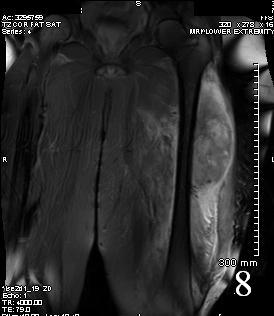

Fig. 7

Fig. 8

Fig. 7-8 Axial (Fig. 7) and coronal (Fig. 8) T2W shows heterogenous high signal intensity